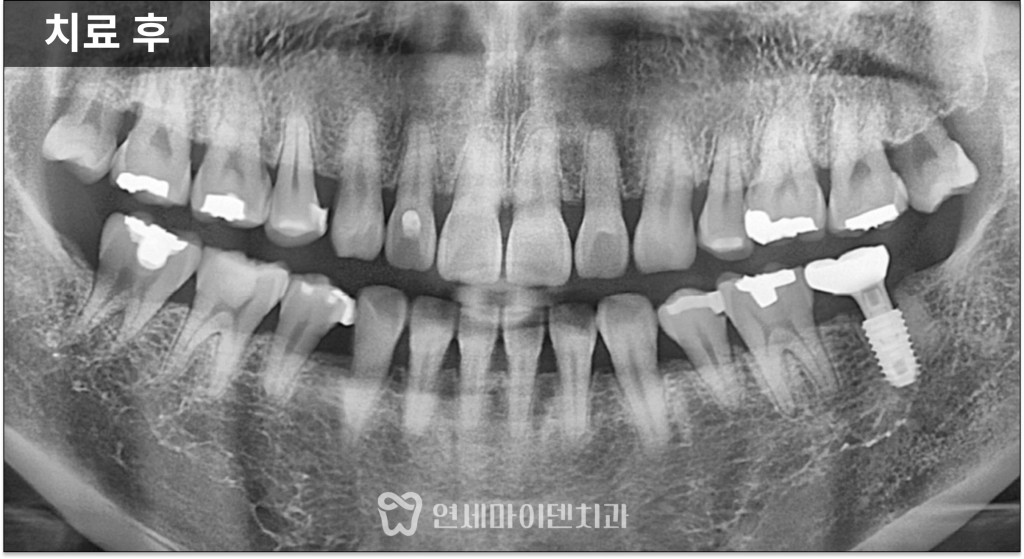

이 방법은 염증을 완전히 제거한 뒤

남아 있는 건강한 뼈를 이용해

즉시 고정력을 확보할 수 있을 때 가능한 치료입니다.

특히 아래 어금니 부위는

하치조 신경관이 지나가기 때문에

위치와 깊이를 매우 신중하게 설정해야 합니다.

염증 조직을 깨끗하게 제거하고

신경 위치를 고려해 식립을 진행했으며,

한 번의 수술로 발치와 임플란트를

모두 마무리했습니다.